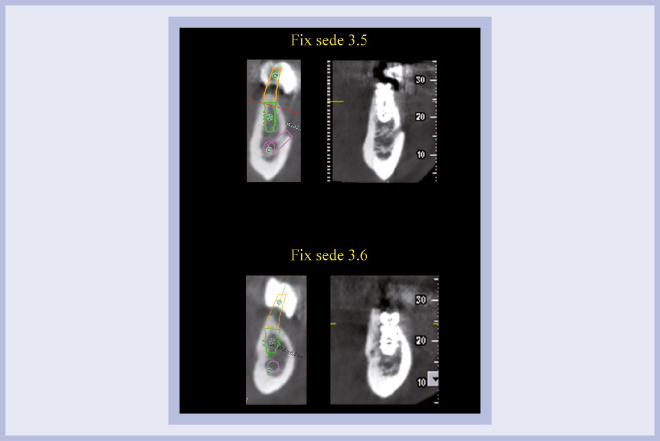

Per riabilitare la masticazione del terzo quadrante, con osso gravemente atrofico, si procede allo studio del caso con esame radiologico 3D e posizionamento virtuale di impianti Exacone® Leone. La prima valutazione è stata eseguita con il software dell’apparecchio radiografico Cone Beam presente in studio. Dopo aver verificato che la quantità di osso residuo fosse sufficiente all’inserimento di due impianti, seppur di dimensioni ridotte, in sede 3.5 e 3.6 senza l’ausilio di tecniche di rigenerazione ossea (Figg. 1-3), si richiede al laboratorio di confezionare una mascherina radiologica con ceratura diagnostica radiopaca e repere standardizzato a livello incisale come da protocollo Leone (Figg. 4, 5). Si verifica quindi clinicamente l’assenza di mobilità della mascherina dopo il posizionamento nel cavo orale del paziente (Figg. 6, 7). Si effettua una CBCT con la mascherina in posizione e l’esame viene inviato in formato DICOM all’azienda Leone assieme al modello master della paziente. L’azienda provvede quindi ad inviare agli Autori il software 3Diagnosys (software di progettazione) in licenza monopaziente con caricati i file DICOM ricevuti; il software viene quindi utilizzato per la progettazione definitiva del caso (Figg. 8-12).

- Figg. 1-3 – Esame Cone Beam iniziale, si verifica la fattibilità di inserimento impianti

- Fig. 2 mento impianti

- Fig. 3